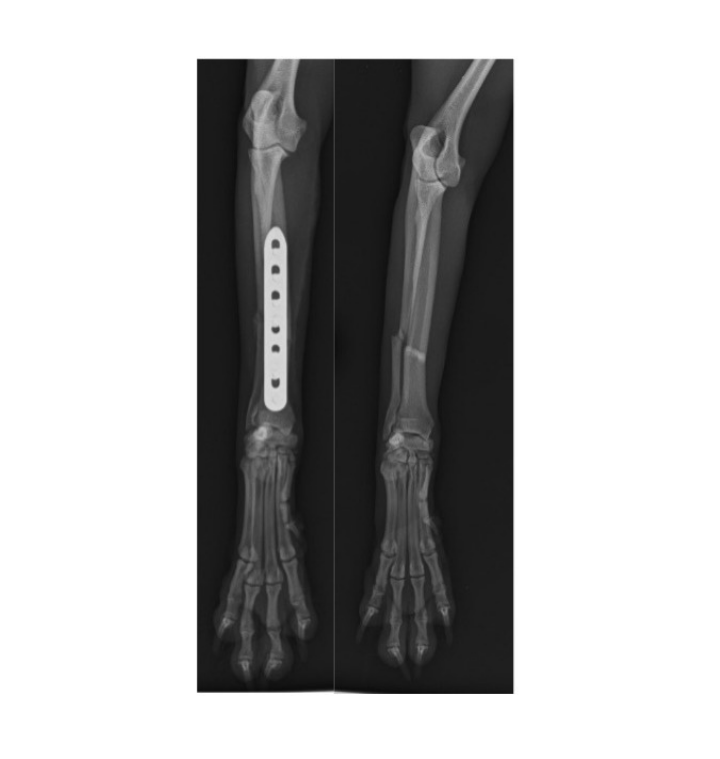

Fracture Repairs

When injuries occur, timely intervention matters most. Our team can perform emergency fracture repairs often within just 24 hours of the injury. If specialised equipment is required, we order it promptly typically with a 1–2 day delay during weekdays. While we await the gear, your pet remains safely hospitalised with pain relief and attentive care throughout.